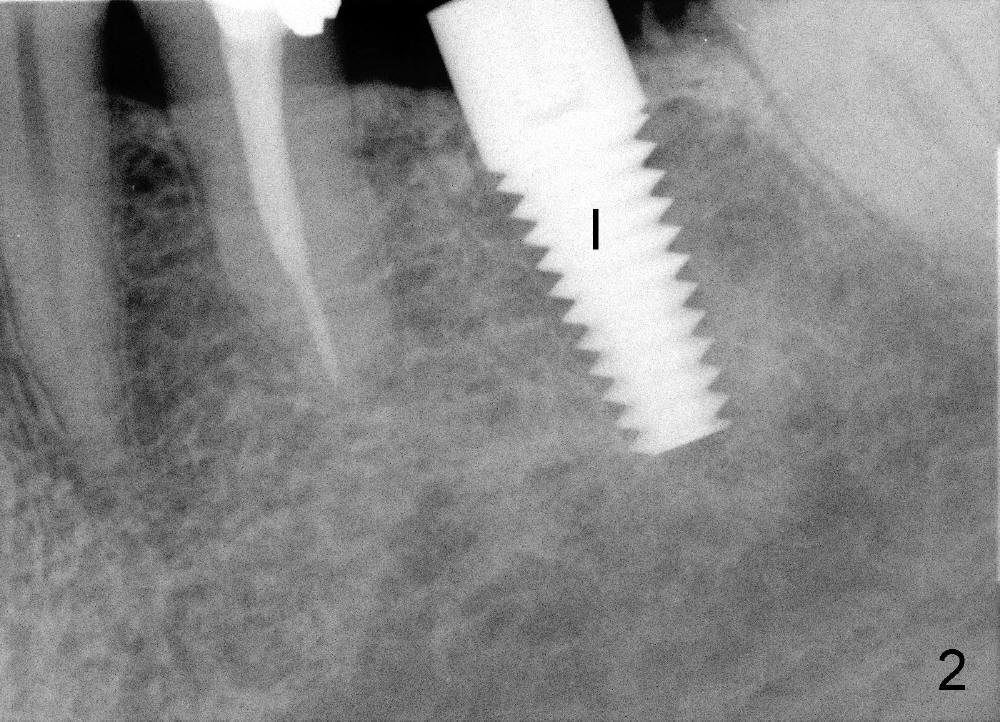

Mr. Zhou is in his fifties. Finally he starts implant restoration. But he has financial constraint. It appears that implant restoration at the site of #19 is the most rewarding in term of restoration of his mastication with a single implant (Fig.1). The implant is apparently placed at the proper level (Fig. 2: I, 6x17 mm). The implant is osteointegrated with minimal bone resorption at crest six months later (Fig.3). The teeth #15 and 18 cannot occlude when 4.5x5 mm abutment (Fig.4: A) is placed at #19 implant (<). It takes a while to trim the unipost from the top gradually in order to let #15 and 18 have normal occlusal contact (Fig.5 mirror image). By that time, the abutment is approximately 2.5 mm tall.